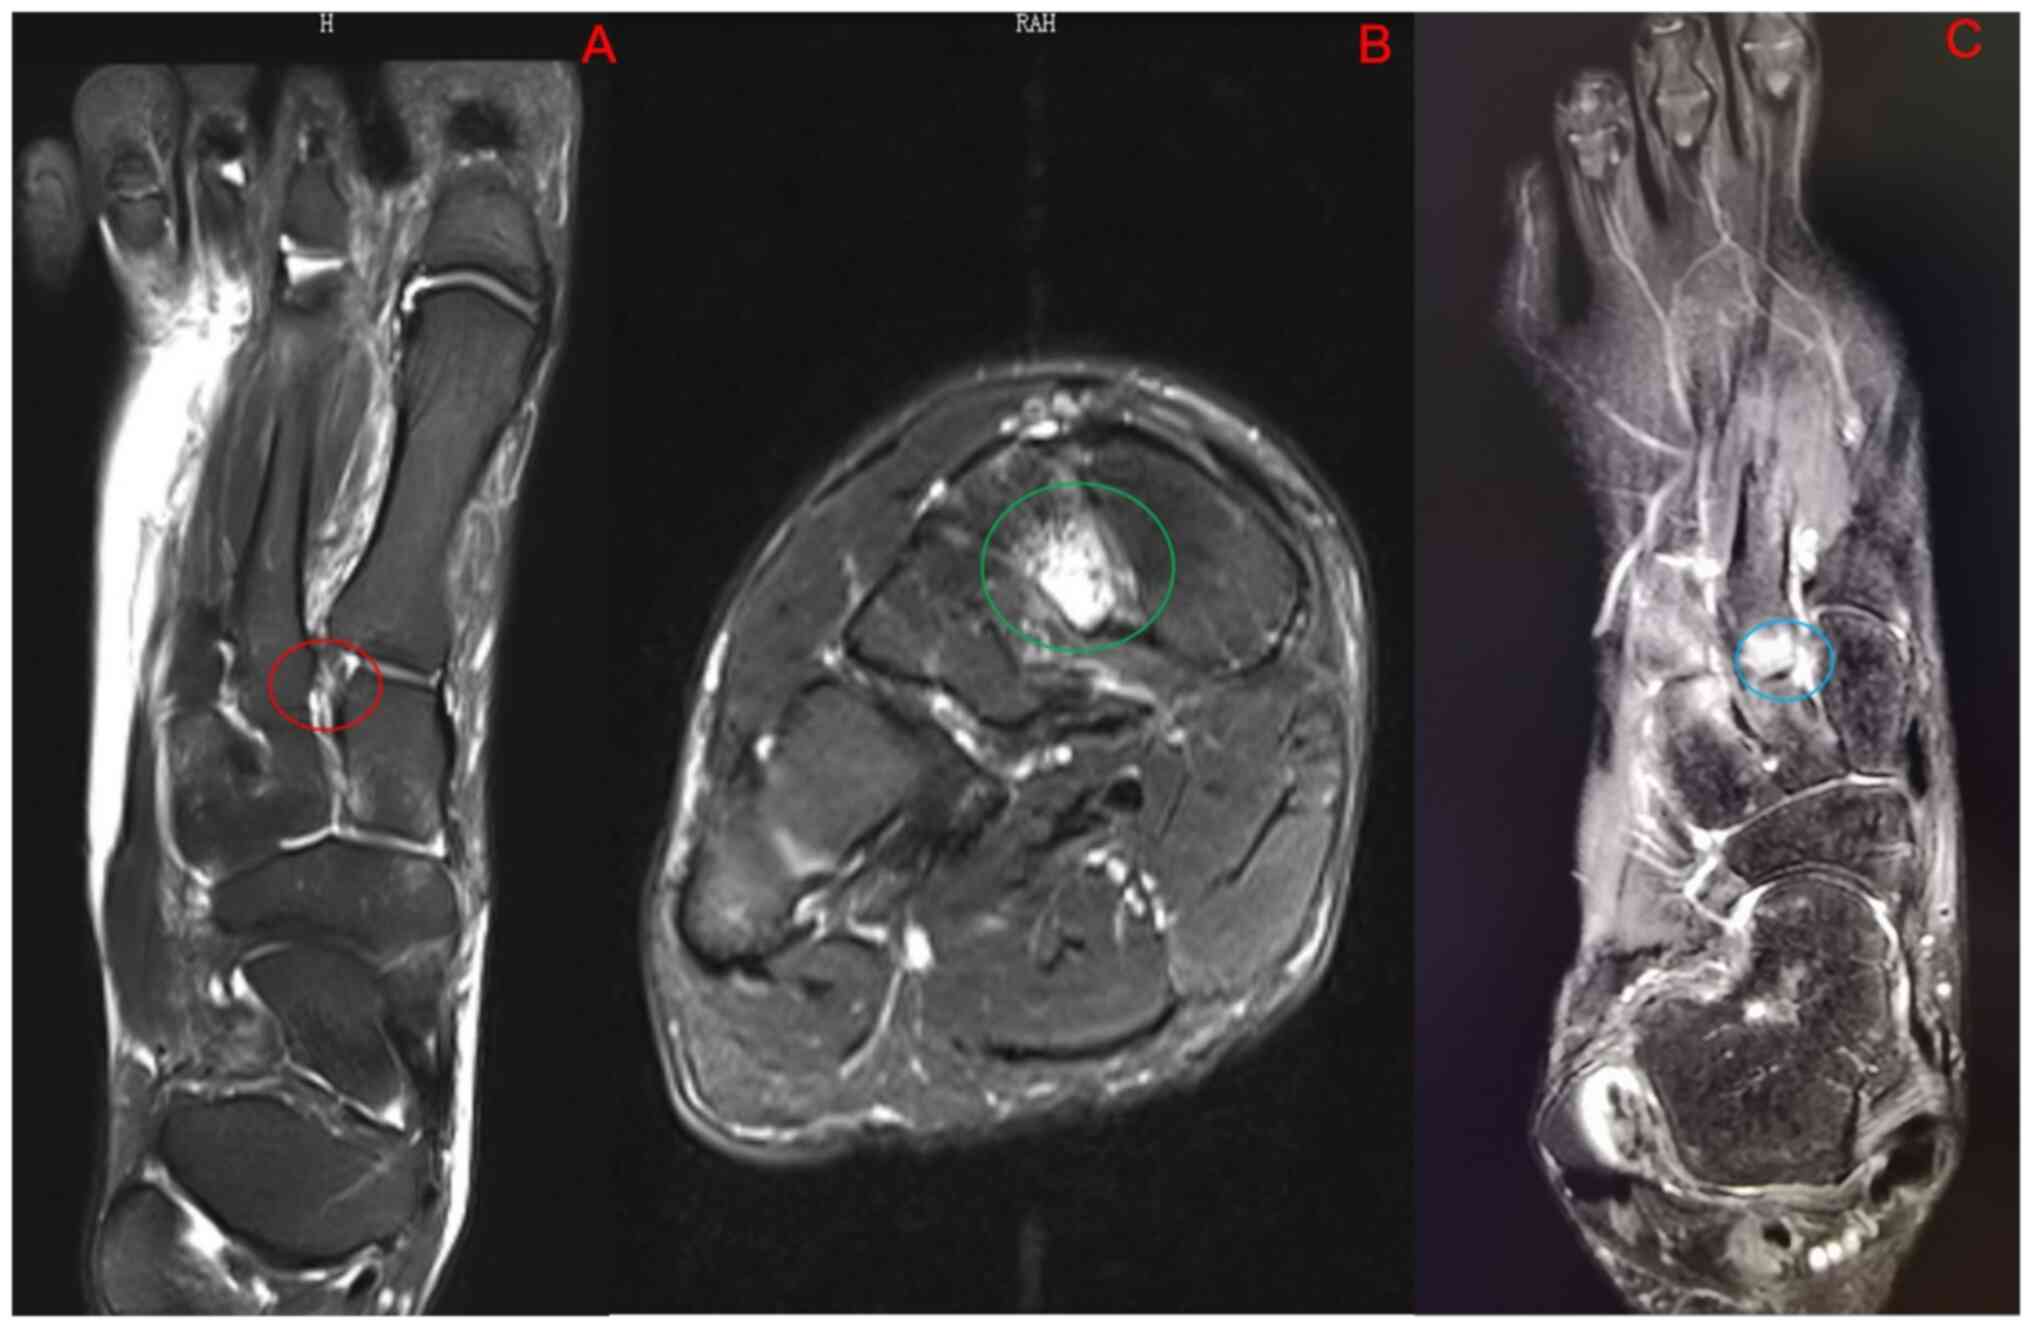

Comparison of diagnostic performance of X‑ray, CT and MRI in patients with surgically confirmed subtle Lisfranc injuries

The present study aimed to compare the diagnostic performance of three imaging tests: X‑ray, computed tomography (CT) and magnetic resonance imaging (MRI), for subtle Lisfranc injuries and three anatomical subtype injuries. The non‑weight‑bearing X‑ray, CT and MRI imaging results of patients with subtle Lisfranc injuries from September 2013 to March 2022 were retrospectively reviewed. Subtle Lisfranc injuries and three anatomical subtypes (first, second and cuneiform rays) were diagnosed based on the surgical reports. The diagnostic performance of X‑ray, CT and MRI was compared. The sensitivity (Sn), specificity (Sp), positive predictive value, negative predictive value, area under the receiver operating characteristic curve (AUC) and κ coefficient were reported. A total of 31 patients were included in the study. The correct diagnosis was made in 48.4% (15/31), 87.1% (27/31) and 96.8% (30/31) of patients by X‑ray, CT and MRI, respectively. A total of 54 different anatomical injuries were found intraoperatively in all patients, with MRI and CT having high agreement (Sn, 72.2 and 87.0%; κ, 0.69 and 0.78, respectively) and X‑ray having a low agreement (Sn, 29.6%; κ, 0.26) with the surgical findings. Regarding the first‑ray injuries, CT had the highest Sn (76.9%), Sp (100%) and AUC (0.885) in diagnosing subtle Lisfranc injuries. MRI showed the best Sn (88.5 and 93.3%, respectively) and AUC (0.942 and 0.904, respectively) in both second and cuneiform rays. In conclusion, non‑weight‑bearing X‑rays had poor diagnostic accuracy for subtle Lisfranc injuries and their subtypes. CT was superior to X‑rays and MRI in diagnosing first‑ray injuries. Although not significantly different from CT in terms of overall diagnosis, MRI was superior to X‑ray and CT in diagnosing second and cuneiform‑ray injuries.

Figure 2